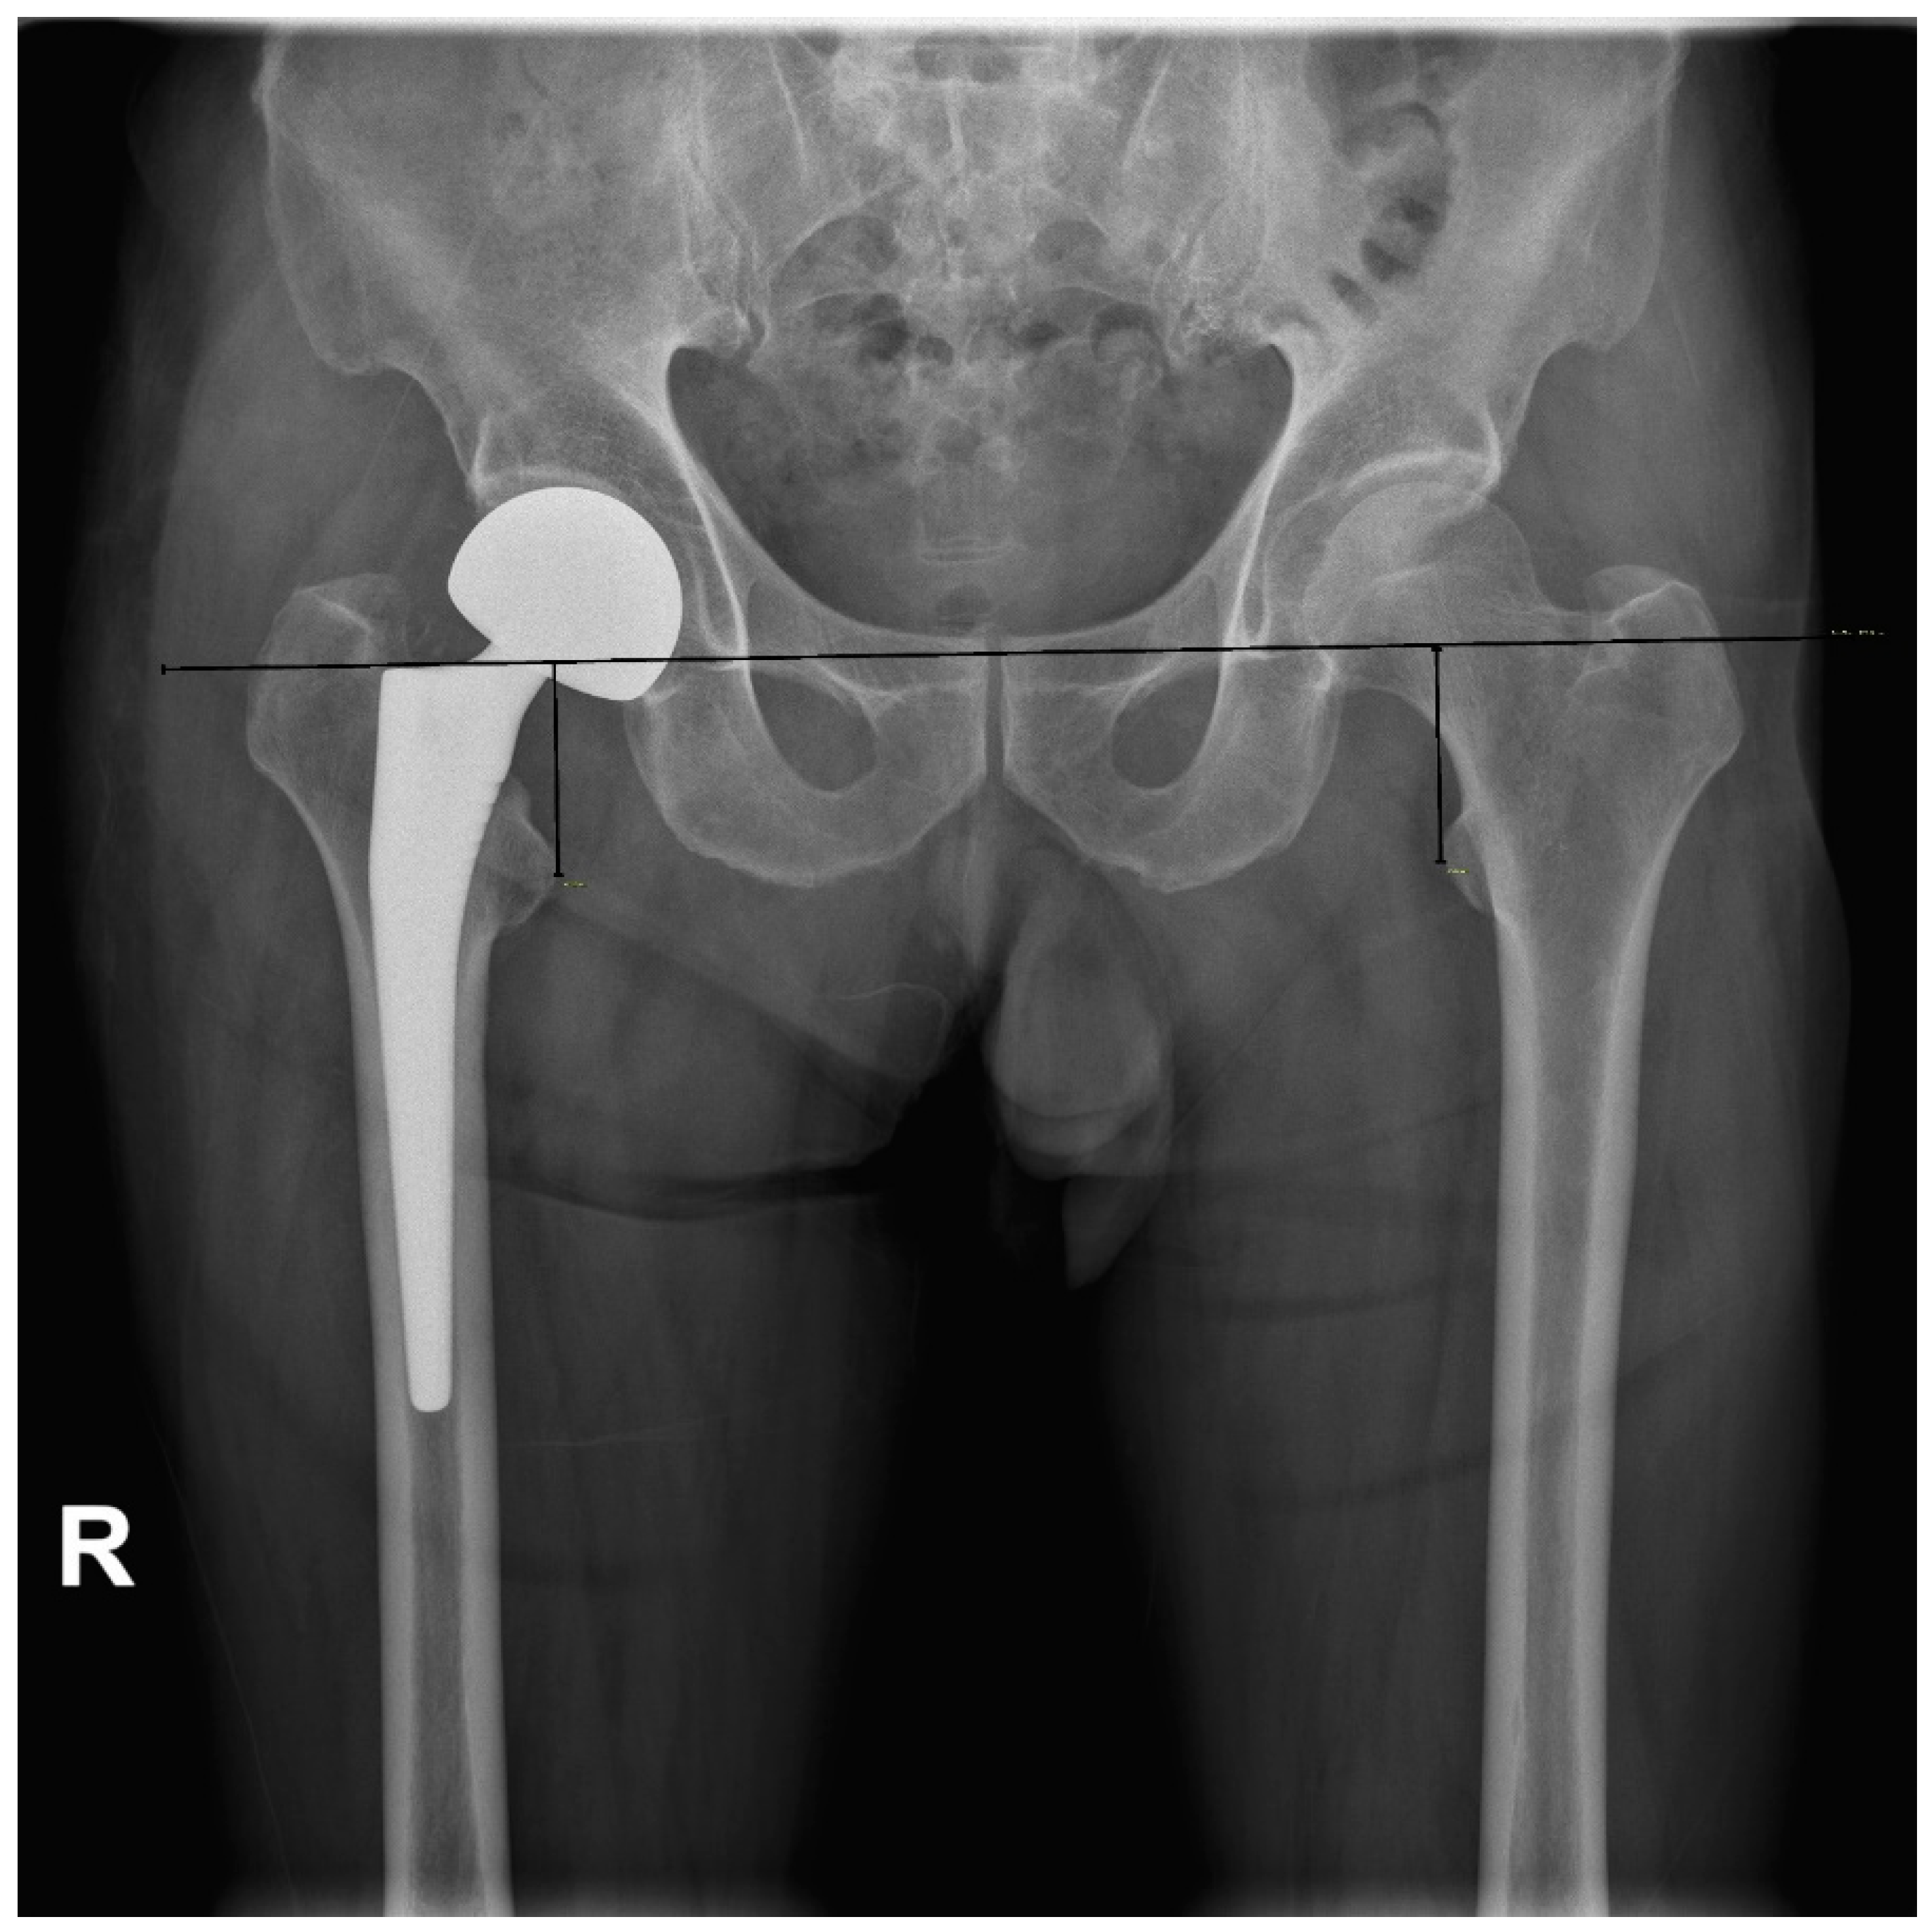

2.2. Radiologic Parameters

| Mean LLD | 1.6 ± 1.2 | 1.1 ± 1.2 | 0.024 |

| <2 mm | 22 (34.4%) | 44 (68.8%) | |

| 2–4 mm | 37 (57.8%) | 16 (25.0%) | |

| 4–6 mm | 4 (6.3%) | 4 (6.3%) | |

| ≥6 mm | 1 (1.6%) | 0 (0.0%) | 0.001 |